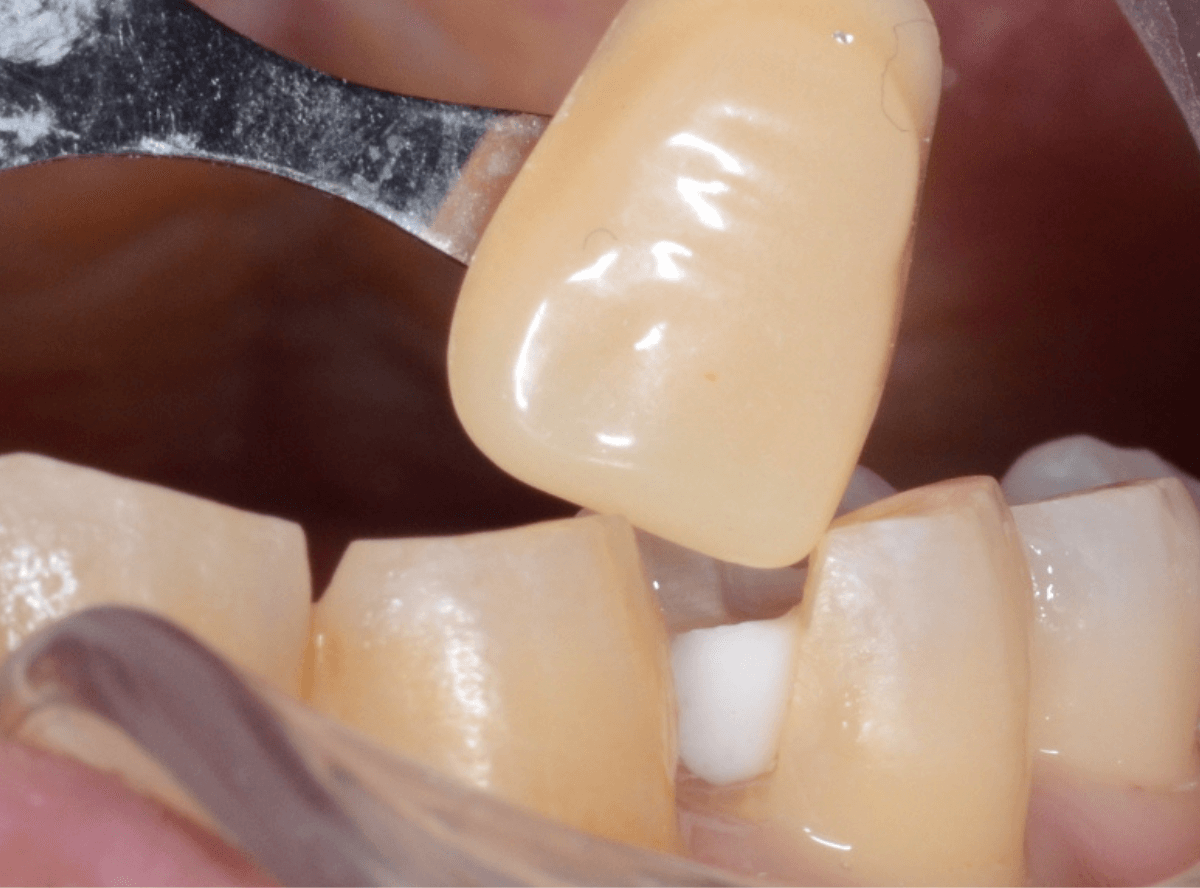

以前に治療した上のさし歯を綺麗にやり直したいというご相談の患者さんです。

保険診療で行うさし歯「レジン前装冠」が入っています。

「レジン前装冠」は裏から撮影した写真を見ていただければわかるように、銀歯の上にレジン(プラスチック)を盛ったさし歯で、実質的には銀歯です。

銀歯の上にプラスチックを盛るために、歯をかなり大きく削る必要があったり、短期間で劣化・変色する(この方の差し歯も劣化してのっぺりした黄土色になっています)、金属の色素が歯肉に溶け出して歯肉が黒くなる(メタル・タトゥー)などのデメリットがあります。

この形に合わせた仮歯を製作し、歯肉が落ち着くまでしばらく経過観察します。

痛みが引き、歯肉の形が整ってきたところで、型をとってさし歯を製作します。

今回は、ジルコニア・セラミックで製作する事になりました。

模型上で精密に制作します。

ジルコニア・セラミックは歯の内側や見えない部分にも一切金属を使用しないさし歯ですので、治療後の金属色で悩むこともありませんので、オススメです。

お口の中でsetしたところです。